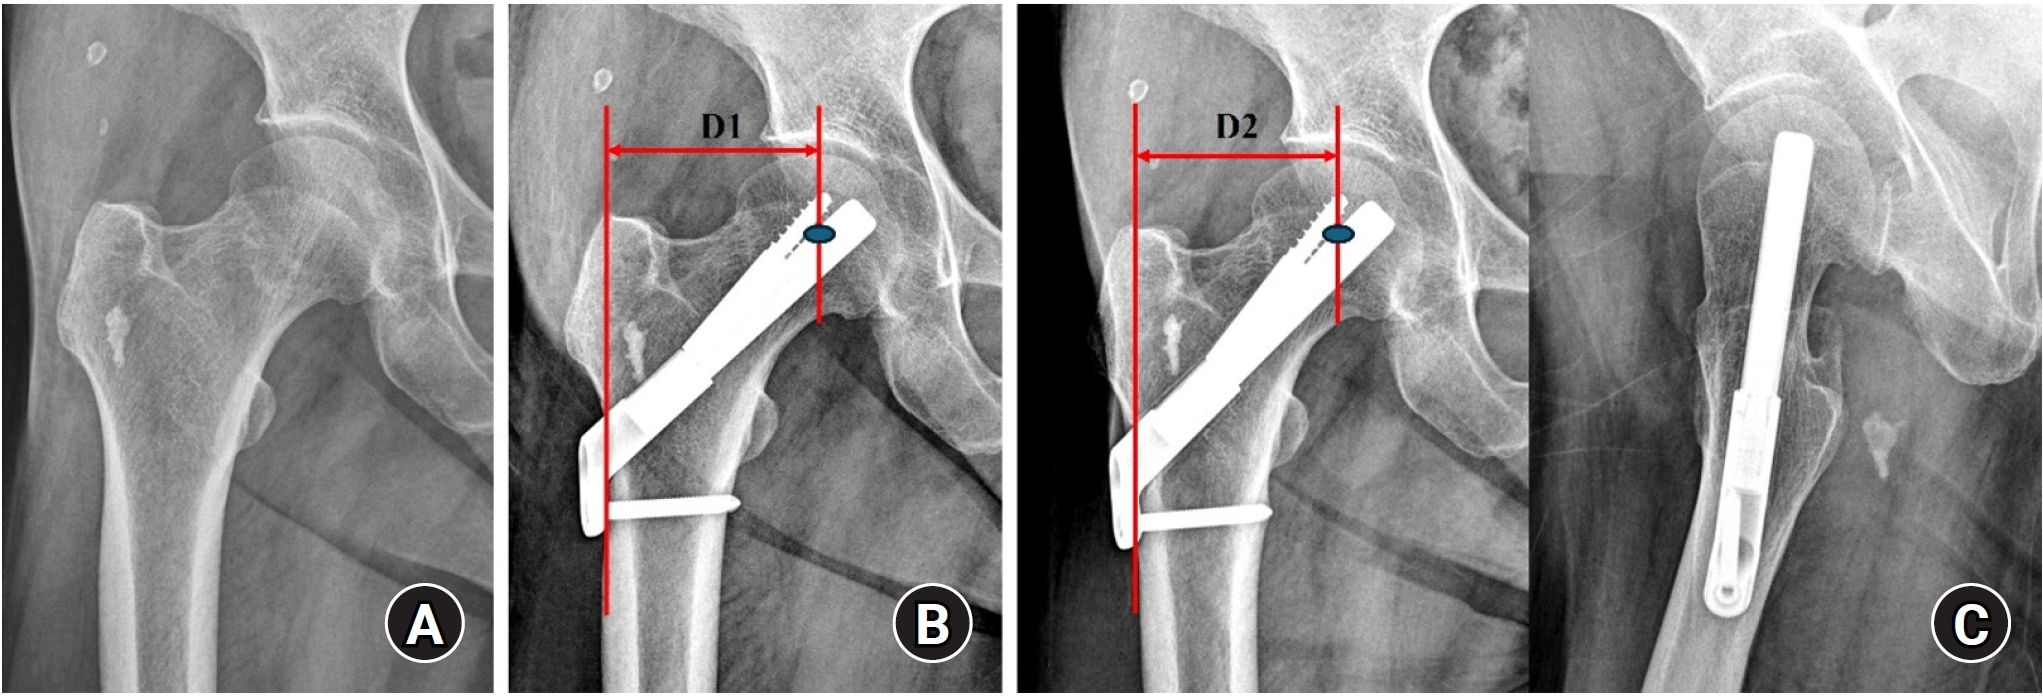

Radiological outcomes

At the final follow-up, the union rate was 87.5% (21/24) in the FNS group and 95.8% (23/24) in the DHS group, with no statistically significant difference between the two groups (P=0.296) (Figs. 2, 3). The mean femoral neck shortening was measured at 6.1 mm in the FNS group and 5.9 mm in the DHS group, and no significant difference was observed (P=0.427).

Fig. 3.

(A, B) An 86-year-old female patient with a stable right femoral neck fracture treated with a dynamic hip system. (C) Postoperative 1-year anteroposterior and axial radiographs show a well-healed fracture site and no complications related to the implant.

Fig. 3. (A, B) An 86-year-old female patient with a stable right femoral neck fracture treated with a dynamic hip system. (C) Postoperative 1-year anteroposterior and axial radiographs show a well-healed fracture site and no complications related to the implant.